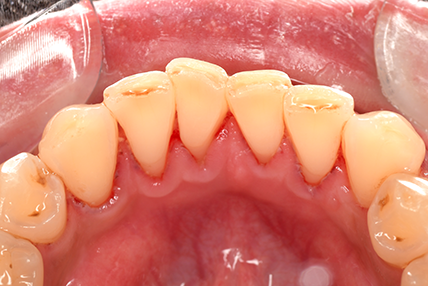

CASE 2

Before

After

基本情報

| 年齢・性別 | 30代・男性 |

| 主訴 | 歯石を取りたい |

| 治療内容 | 超音波スケーラーでの歯石除去 |

| 治療期間 | 60分 |

| 治療費 | 初診料を含め約4,500円 |

| リスク・副作用 | 歯ぐきに違和感や痛みを覚える場合がある。 1週間程度、歯を磨くといつもより出血することがある。 腫れていた歯ぐきが引き締まることで歯ぐきが下がった様に見える。 歯ぐきが下がることで歯がみしやすくなることがある。 一時的に歯の動揺(ゆれ)が増す場合がある。 |